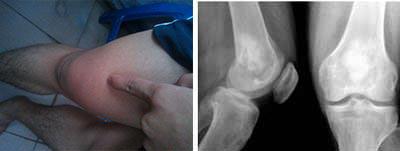

(图:患者治疗前膝关节红肿)

T37℃,P80次/分,R20次/分,BP110/80KPa,巩膜无黄染,浅表淋巴结不肿,无颈静脉充盈,双肺呼吸音清,心律齐,下膝关节疼痛,肘关节疼痛,膝关节红肿明显,脊柱四肢无畸形。

类风湿因子60 IU/ml,抗链球菌溶血素287.1u/ml,血沉20mm/h,超敏C反应蛋白19mg/L。

赵先生长期生活在潮湿生活环境中,2011年9月,出现双膝关节游走性疼痛症状,自行买来止痛药服用后,疼痛缓解。但是快速阴雨天时,关节疼痛再次发作,且遇冷关节发僵发白,疼痛无比。吃止痛药无效后,去医院检查,医生诊断为风湿性关节炎。接受药物治疗三年,膝关节出现红肿现象,关节屈伸不利,食欲下降,晨起关节僵硬持续一小时。2014年8月,多方打听后,来到我院求助主治医生。